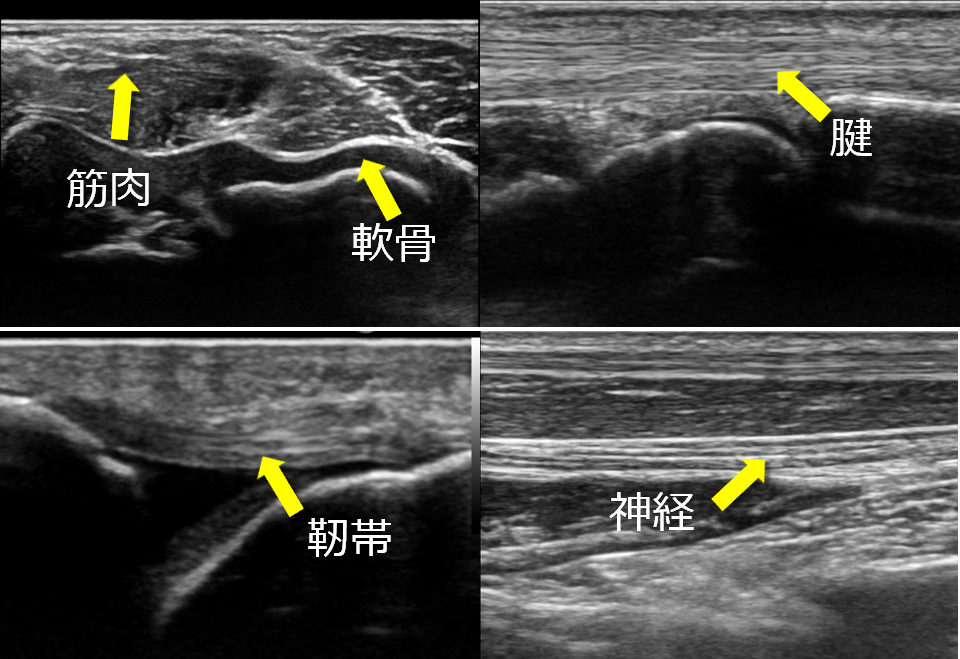

一般的に整形外科というとレントゲンのイメージ強いかと思いますが、超音波を用いることで、レントゲンでは見ることが出来ない、骨以外の軟骨、神経、筋肉、腱、靭帯、血管などを確認し、さらにリアルタイムで血流や動きを観察することが可能になります。

このリアルタイムで動きを見ることができるという点において、超音波検査は優れていると言えます。さらに、超音波装置の性能がよくなり、画像が鮮明にはっきりと見えるようになったことで、今まで見えなかったものが見えるようになりました。すると、病態を把握するという診断はもちろん、針を刺す行為である穿刺や注射、麻酔などを行う際の安全性や確実性も向上します。これらのメリットから、近年超音波は注目を浴び、整形外科に取り入れようとする動きが出始めています。